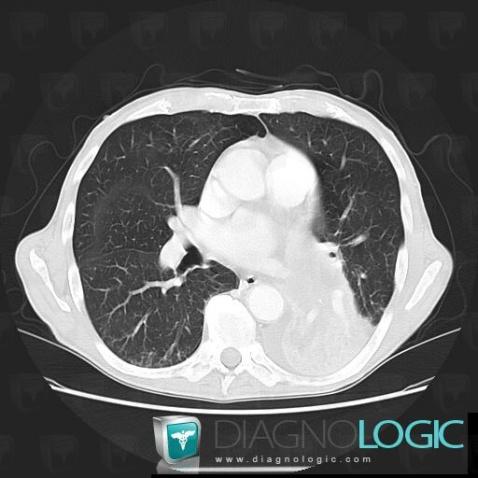

Obstructive pneumonia, Pulmonary parenchyma, CT

Here is the specific information in the key image above:

- Diagnosis Obstructive pneumonia, Location(s) Pulmonary parenchyma, with gamuts Chronic consolidation, Localized consolidation